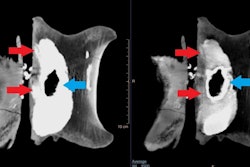

The SpaceOAR works by placing a small amount of gel between the prostate and rectum, a prostate spacer, to increase the distance between them and thus reduce the radiation dose received by the rectum during treatment.